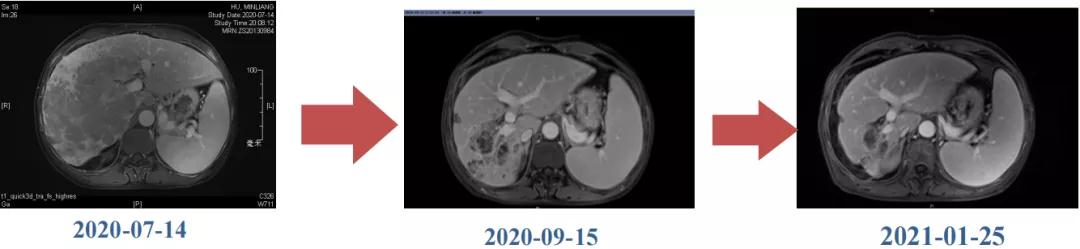

Δ肝脏MRI,最大肿瘤18.4cm

肿瘤学评估(用药后2个月对比6个月):肝内主瘤明显缩小,动脉期强化降低;子灶消失;门脉右支癌栓明显缩小坏死;肺转移灶缩小,大部分消失。

Δ治疗过程中病灶影像学变化